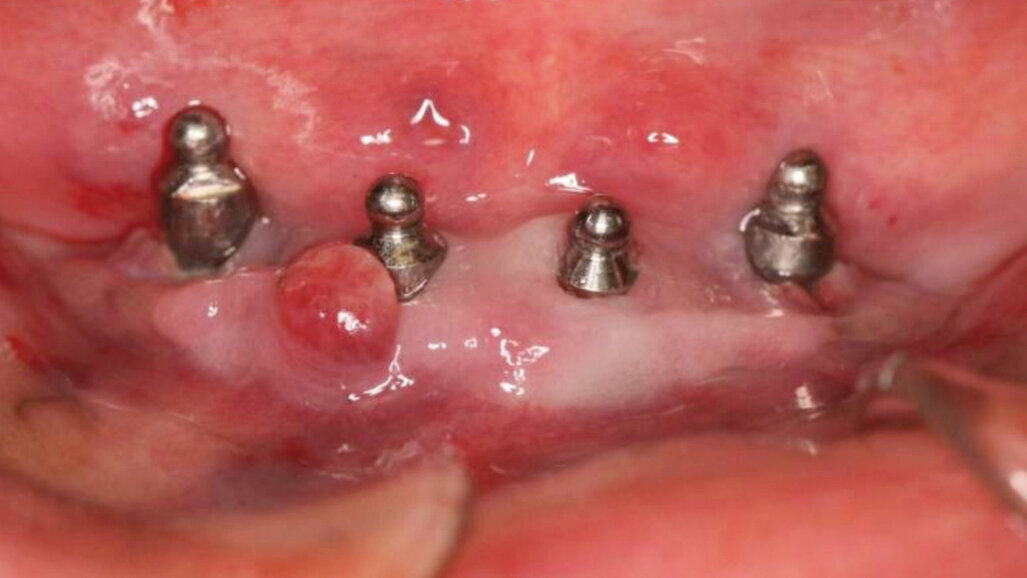

Mme M. N.

Situation initiale défavorable : 76 ans, hygiène très défavorable, xérostomie, candidose buccale, prothèse inadaptée, non-passive, absence de vestibule. Péri-implantite évoluant depuis 2004, première consultation dans notre cabinet juillet 2010. Un traitement non-conservateur semblait indiqué : dépose des implants et curetage, associé secondairement à une reconstruction osseuse et de muqueuse kératinisée si besoin. Mais le contexte dentaire de la patiente ainsi que la difficulté à gérer la temporisation (problèmes d’alimentation chez cette patiente très fragile) nous ont poussés à essayer de préserver ses implants très infectés, qui présentaient des poches péri-implantaires de plus de 13 mm.